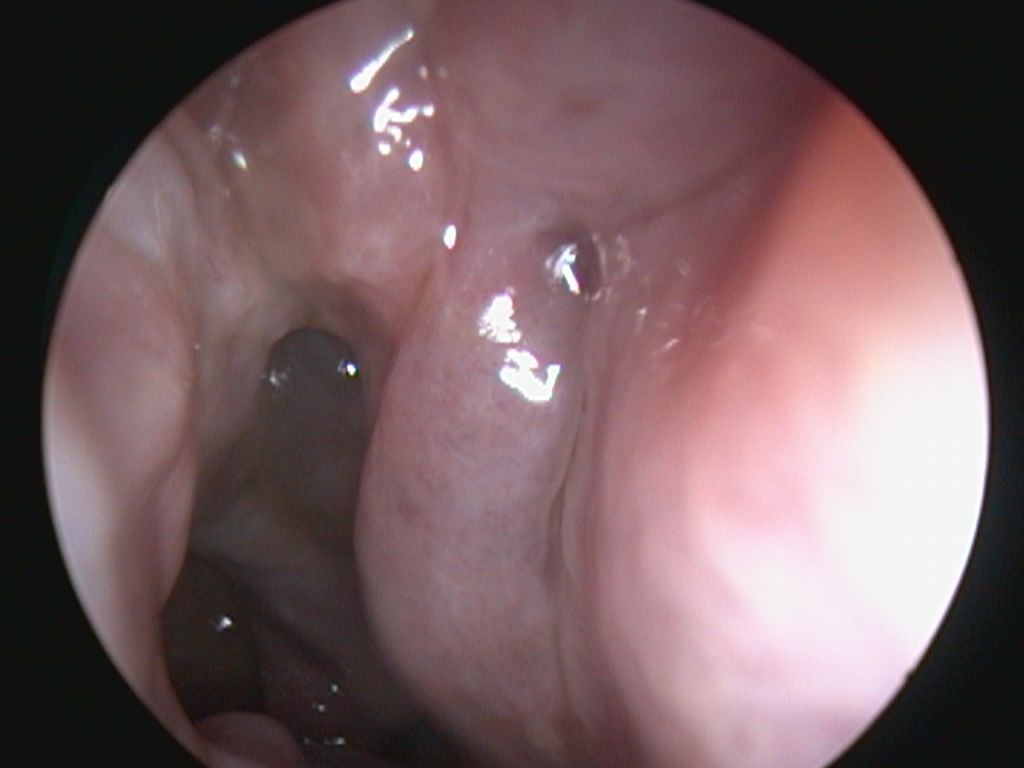

The Research Coalition of the Snot Force Alliance recognized the need for a better way to grade sinonasal polyps after sinus surgery. The standard nasal polyps scales did not adequately measure what otolaryngologists and rhinologists see clinically on endoscopy. The Postoperative Polyps Scale (POPS) was developed to assist otolaryngologists clinically and during clinical trials assessing grade of sinonasal polyposis after surgery.